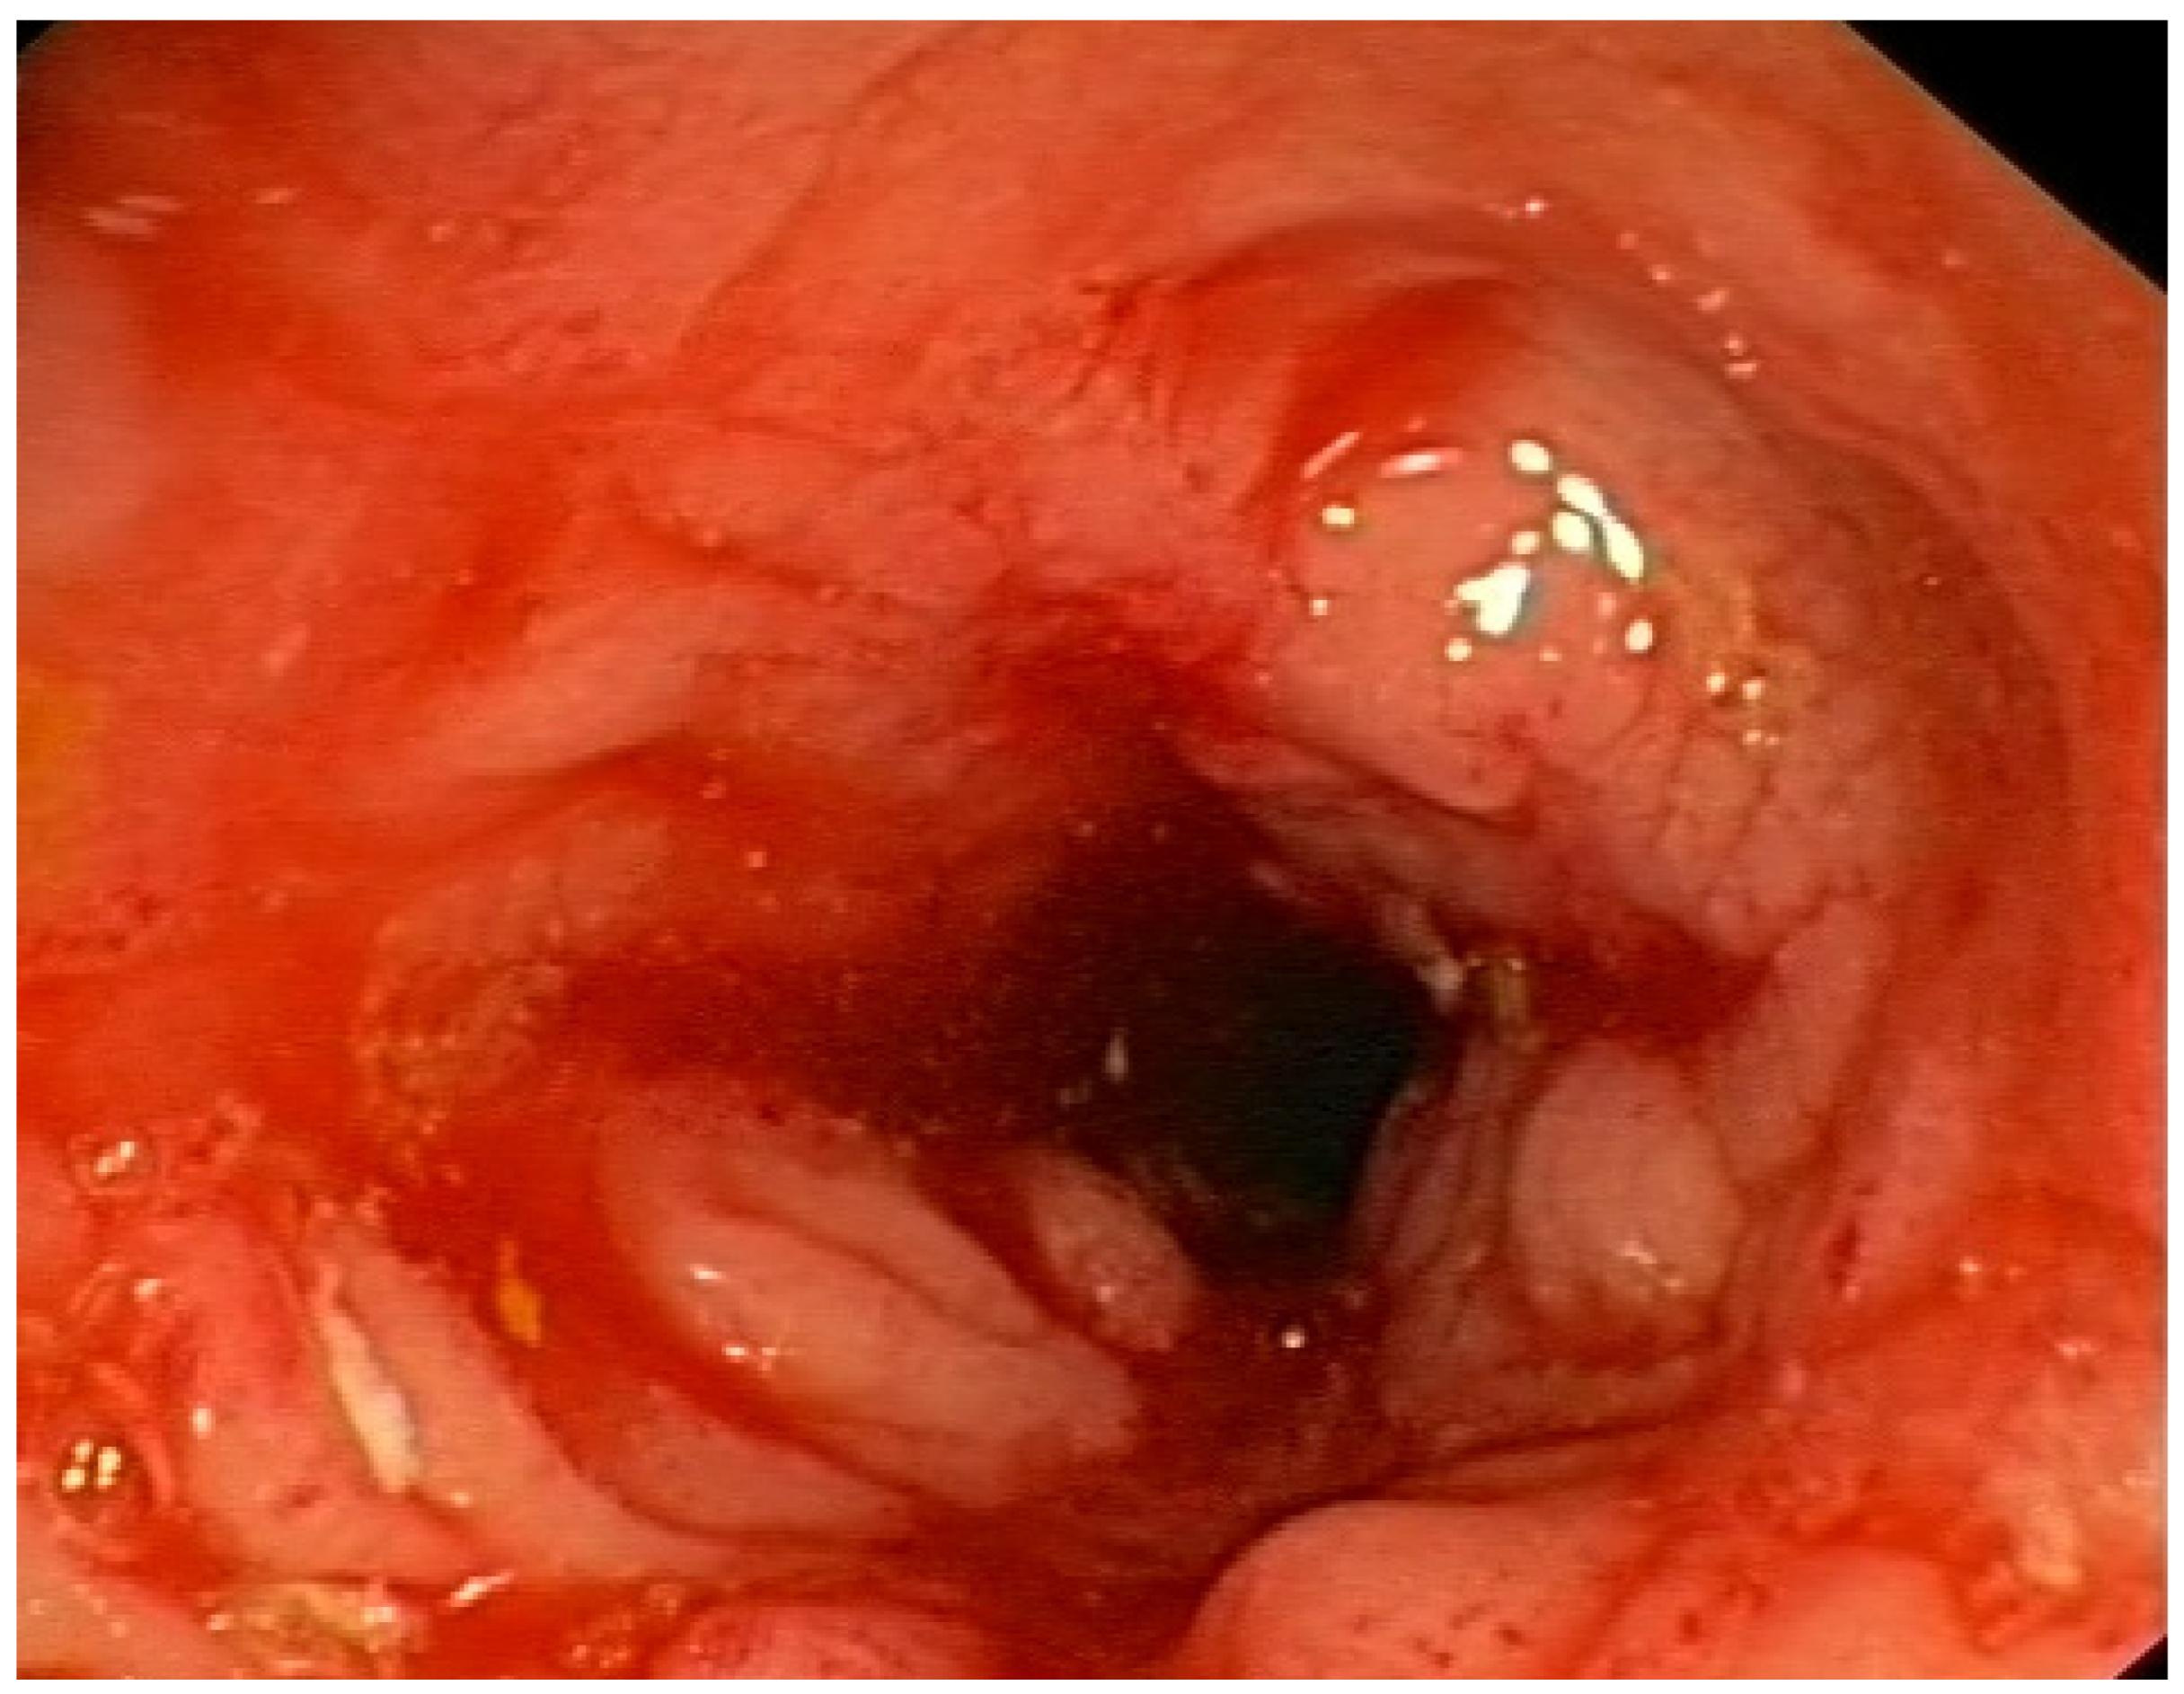

Figure 5.

Ulcerative mucositis in the large intestine of a patient with Crohn’s disease.